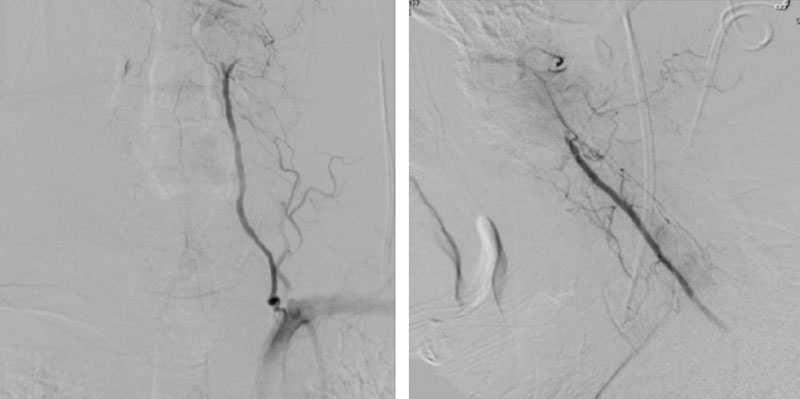

The patient was brought to the operating room, and general tracheal anesthesia was initiated via fiberoptic approach. Somatosensory potentials, motor evoked potentials, and brainstem auditory evoked responses were recorded. The patient then underwent intraoperative angiography of the right Vertebral Artery performed via a 5 French Right Radial Artery access. Once it was established that he had good flow, a Mayfield head holder was attached to the patient’s head on the 60 pounds of torque pressure. The Wilson frame attached to the Jackson table was then placed on top the patient attached to the Jackson frame. The patient was secured with straps and bed sheets and then positioned prone by rotating the frame around its axis. The flat plate of the Jackson table was then removed, and the patient bony prominences and soft tissues were adequately padded. Angiography was then again repeated showing good flow through the Vertebral Artery. After that, after being properly secured to the table with access to the right radial sheath, the neck and the left posterior iliac crest area and a tricortical autograft was then obtained with osteotomes. Iliac crest was reconstructed with fiber graft allograft. Posterior cervical incision was then performed and the spinous processes of C2 and C3 were identified and cleared of the fascia and then the muscle the way to the lateral edges of lateral masses. The C1 posterior ring was completely subluxed under the occiput and C2 lamina. The patient evoked potentials remained stable. The C1 lamina was then cleared of the soft tissue laterally on both sides. On the left side, significant osteophyte formation was visualized, and the C1-2 foramen was completely closed by the bone. On the right side, the C1-2 foramen was dissected, and the veins were coagulated with bipolar cautery. The C2 nerve root was identified and then coagulated bipolar cautery and divided with micro scissors, completing the planned C2 rhizotomy. The decision was made to perform an occiput to C3 fusion, since the articulation between the occiput, C1, and C2 was technically difficult and most likely would result in an inadequate fixation. At that point, a small occipital plate was brought into the field, and secured to the suboccipital bone with 14- and 12-mm screws. Then a pilot hold was created into the lateral masses of C3 bilaterally. The C3 appeared to be solidly fused to C2. First a hole was made with the drill and then passes were made with 40 mm drill with the guide. There were palpated with a ball-tipped probe and tapped. After the replaced 14 mm lateral mass screws into the lateral masses of C3 bilaterally. After the rods were fashioned and secured to the screw heads and the occipital plate with locking caps. (Figure 6)

Intraoperative angiography was then repeated again, showing good flow through the right Vertebral Artery into the Basilar Artery. Intraoperative fluoroscopy was then also performed to confirm good position of the screws and rods in both AP and lateral projections. (Figure 7)